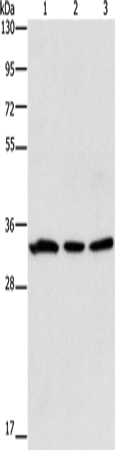

分类: 科研抗体货号: P07340别名: H3.5; H3F3C应用: WB反应种属: Human, Mouse